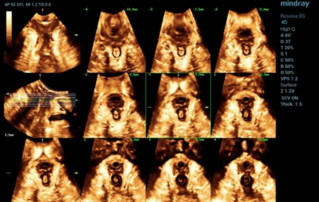

?? ?? ??? ?????(Endocavity volume convex array transducer)(DE10-3WU, Resona 7, ?????)? ??? ??? ???, ??? ?? 1/3 ?? ? ??(anterior vaginal wall)? ???? 18x14 mm ??? ?? ??(an ovoid-shaped formation) with a parietal fine suspension, ????? ??? ???? ??(non-displaced), ????,? CDI ??? ?? ?? ???? ????????. 3D ??? -? ??? ? ??(hyperechoic septa)? ?? ???? ??? ?? ??.

?? ??? ?? ???(Volumetric reconstruction)? ??? ??? ?? ??? ?? ??? ??? ? ??? ?? ??????? ??? ??? ??? ???.